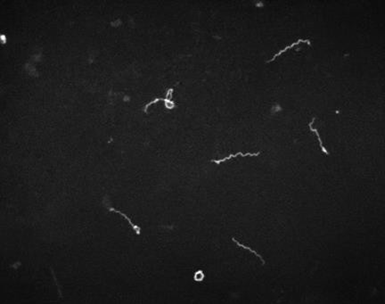

Laboratory diagnosis:Definitive diagnosis is by dark field microscopy performed on body fluids (e.g., nasal discharge) or moist skin lesions demonstrating thin, delicate, corkscrew-shaped organisms with rigid, tightly wound spirals. Failure to identify spirochetes with dark field microscopy does not exclude the diagnosis of syphilis.